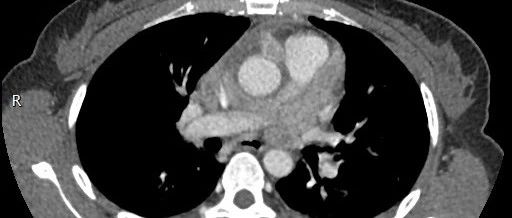

女性,间断胸痛3月,请诊断!

患者,女,58岁,接种流感疫苗后出现咳嗽、乏力和轻度发热就诊。进行短期抗生素治疗后,这些症状仍持续。

老年女性,间断胸痛3月,请诊断!